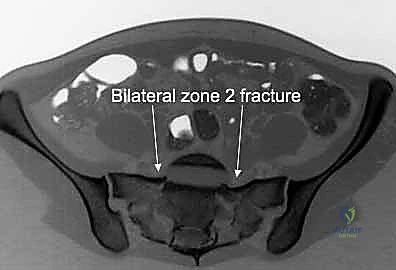

3. التصوير المقطعي المحوسب (CT Scan): وهو المعيار الذهبي (Gold Standard) لتشخيص كسور الحوض والعجز. يقوم الدكتور هطيف باستخدام تقنية إعادة البناء ثلاثي الأبعاد (3D Reconstruction) لفهم هندسة الكسر بدقة متناهية قبل الدخول إلى غرفة العمليات.